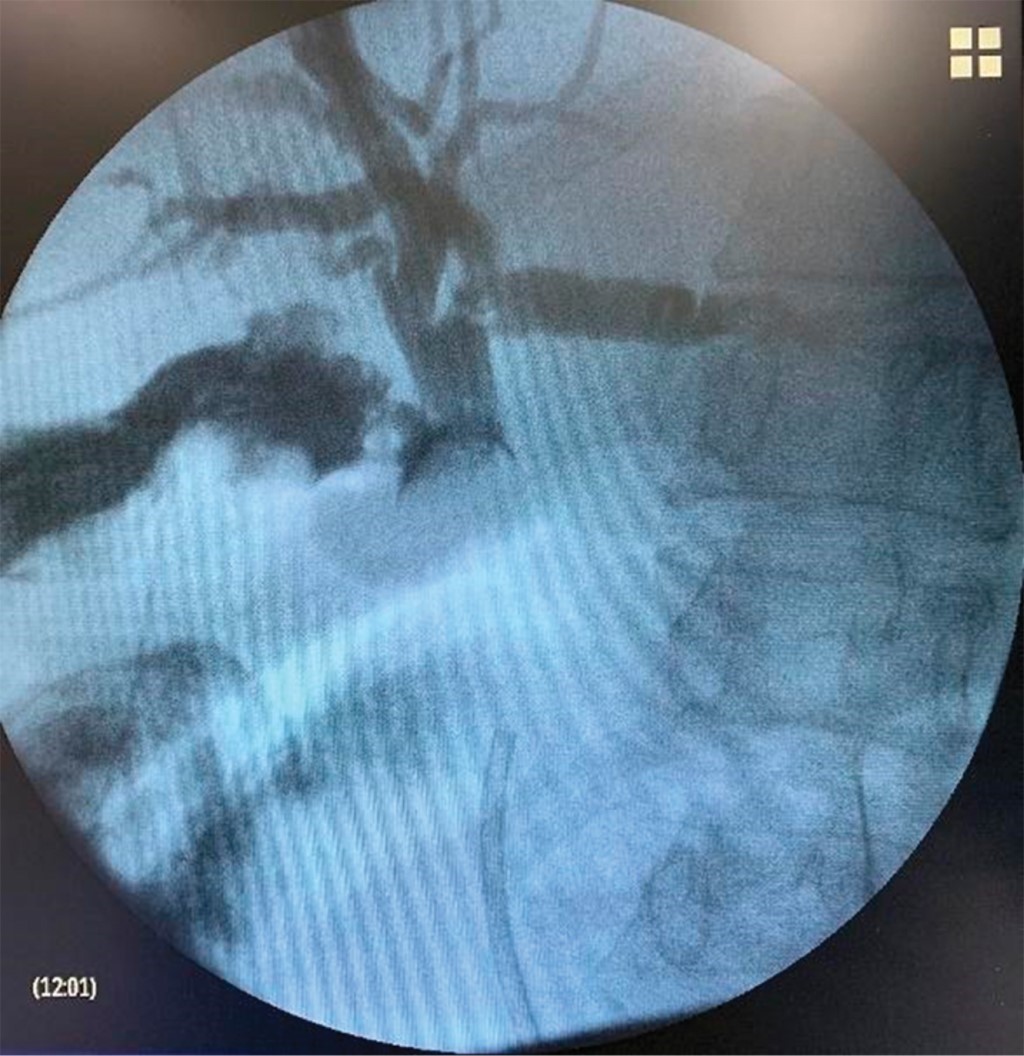

A 72-year-old woman was admitted to our hospital with a diagnosis of Mirizzi syndrome. Endoscopic retrograde cholangiopancreatography (ERCP) and placement of a 10 Fr 10 cm long Amsterdam-type biliary stent were performed in another hospital. Laparoscopic cholecystectomy was attempted on a scheduled basis, but due to the severe inflammatory process, it was decided to convert to open cholecystectomy. We performed trans cystic cholangiography, identifying a common bile duct filling defect (Figure 1). We performed a choledochotomy, the common bile duct stone was removed without the need to mobilize the stent, and a fenestrated subtotal cholecystectomy was performed. A closed suction drain was placed in the subhepatic space. The patient developed a low-output biliary fistula, which was resolved satisfactorily on an outpatient basis without needing specific management. After 15 days, the drainage was removed, management with ursodeoxycholic acid at 15 mg/kg orally was started, and an abdominal ultrasound was requested, which was performed six months later. It showed the intra- and extra-hepatic biliary tract of standard caliber without other alterations; the prosthesis was not visualized at the level of the biliary tract. Liver function tests (LFTs) showed a decrease in transaminase levels concerning preoperative, with aspartate aminotransferase (AST) 24 U/L versus 35 U/L, alanine aminotransferase (ALT) 28 U/L versus 23 U/L, and alkaline phosphatase (ALP) 111 U/L versus 275 U/L without reaching normal levels, and γ-glutamyl transferase at 108 U/L. No further action was taken.

Figure 1